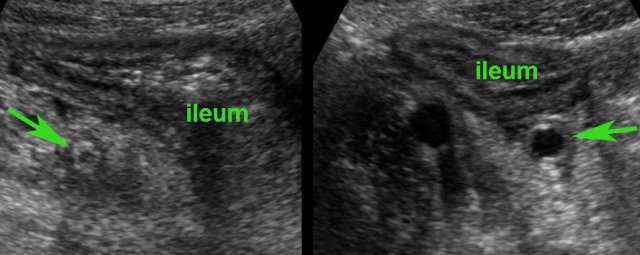

In this young patient, USfindings were compatible with both early Crohn’s ileitis and right-sided infectious ileocolitis.

Repeated US after 7 days waspathognomonic for Crohn’s disease.

Note that both wall thickening and surrounding inflamed fat have markedly increased in volume (arrowheads).